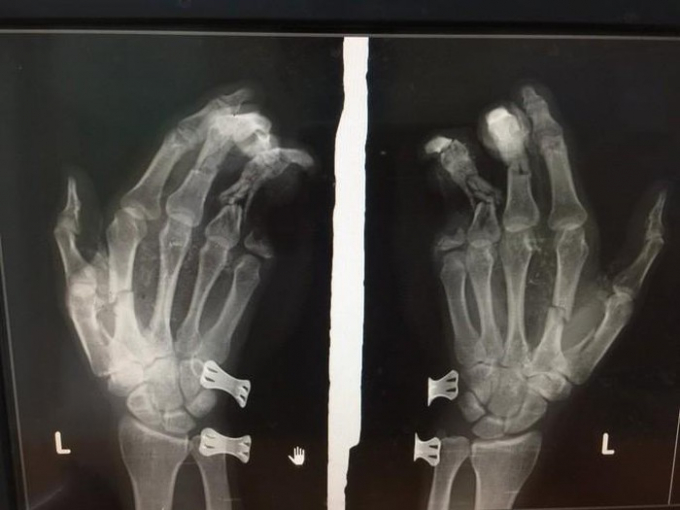

Bàn tay của anh Duy bị tổn thương nặng.

Chiều ngày 27/5, Bệnh viện Đa khoa II Lâm Đồng (đóng tại TP Bảo Lộc) cho biết, đã tiếp nhận một bệnh nhân nhập viện trong tình trạng bàn tay bị tổn thương nặng.

Lúc này, bất ngờ chiếc điện thoại phát nổ. Hậu quả, khiến bàn tay trái của anh Duy dập nát, tổn thương nặng và ngón út bị đứt mất 2 đốt.

Sau khi nhập viện, anh Duy được các y, bác sĩ tiến hành phẫu thuật và khâu lại vết thương.